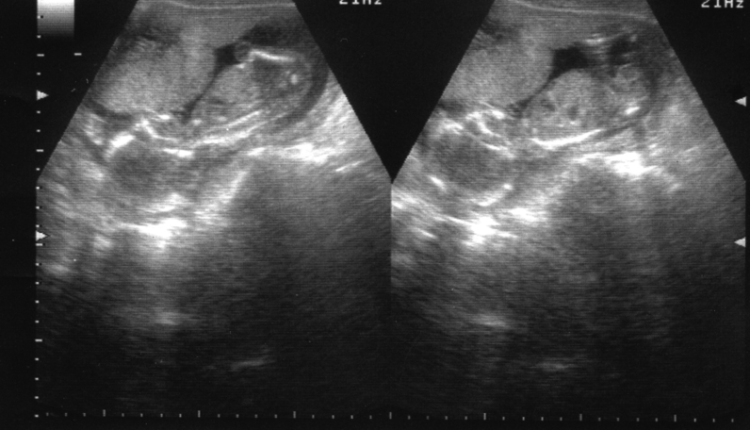

كانت الثلاث أشهر الأولى مريرة ،اغماءات وبكاء بلا سبب واضح،استفراغ وتقزز من الروائح، حتى من رائحة حبيبها ،بعضهن ألزمهن الطبيب بالراحة والاستلقاء على الظهر كله يهون من اجل الطفل …القادم دمعت الأعين عندما سمعوا دقات قلب فلذات اكبادهم وصور ذلك المخلوق الصغير المحشو في الأرحام وهو يكبر مع كل صورة صنتمترات قليلة ،يتشكل بعضلات وهيكل عظمي وعيون جاحظة والركلات التي كانت تتفاعل مع دفء يد الأب او احد الأحباب. تدفق الماء ،ماء الحياة،حملا تلك الحقيبة بكل اللوازم،الحفاظات وأول لباس للبايبي وعطوره ومستلزمات حمامه الأول ،قماطات وغيرها من اللوازم الشخصية ركبا تاكسي،كان صاحب التاكسي منفعلا ،كان يحاول ان يمشي رويدا كي لا يؤلم الأم التي انهكها التوجع ،ولكن طرقات هذا البلد مليء بالمطبات فاخذ الوجع يتعاظم والإيماءات أصبحت صراخا مع كل حفرة وما اكثر الحفر. لم يجدا كرسيا متحركا ينتظرهما ،حملها زوجها بين ذراعيه ،بعد الفحوصات ودفع معلوم الولادة ، لاعنا القائل بان الصحة لدينا مجانية ولكنه تراجع : لن اغضب اليوم ، سأرزق بولي للعهد ولا يجب ان يراني غاضبا .